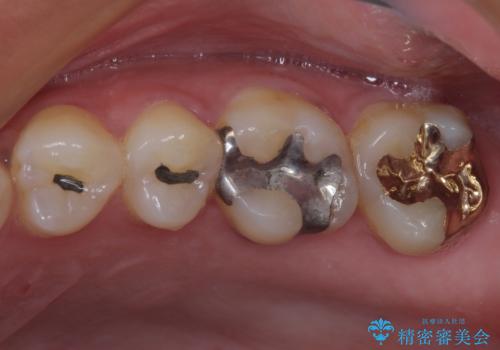

- 奥歯の銀歯がすぐに外れてしまうとのことで来院された患者様です。

何度か銀歯の詰め物を作ったものの、しばらくすると外れてしまうそうで、来院時には銀歯のない状態でした。

咬み合わせをみると、奥歯に負担がかかりやすいことが分かったので、適合がよく、硬さが歯と近いPGAインレー(白金加金合金インレー)にて修復治療を行うこととしました。

ゴールドインレーは銀歯のインレーやセラミックインレーと比べ、「技工操作の精度が高く、適合が著しく良い」というメリットがあります。特に上の奥歯は歯科医師の操作が行いにくいため、「適合の良さ」は再治療のリスクを防ぐ上でとても重要な要素となります。

上の奥歯は金属色が見えることもないため、審美的な問題は全くありません。